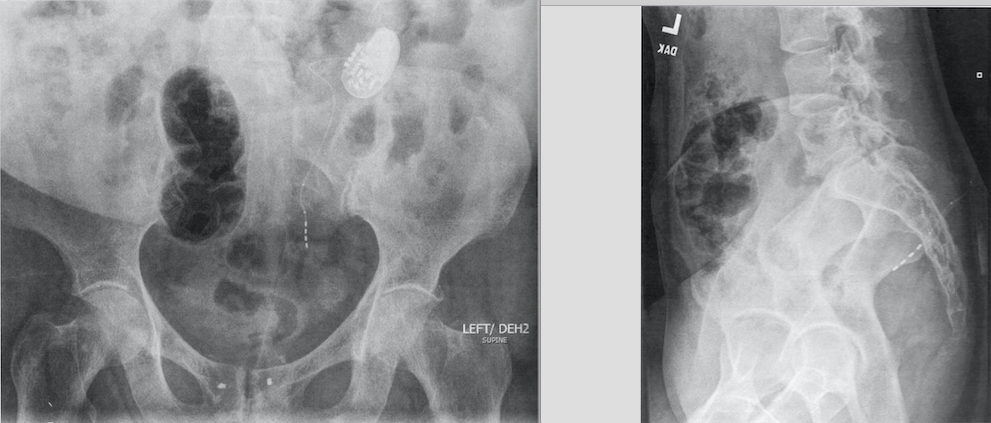

55-year-old woman, who had a sacral neuromodulation implant placed four years ago, has declining efficacy despite several reprogramming sessions. A plain film X ray is shown. The next step is:

D

This plain f ilm AP view shows the lead lateral in the 53 foramen. The lateral view shows it too deeply placed, and this puts her at risk for deep stimulation of S2 roots causing leg and other lower extremity untowa rd stimulation. The use of the curved stylet would allow placement of the lead into S3 in a more media l to lateral conf iguration, thereby, allowing maxima l contact of electrodes to the nerve. This is due to the nerve following a medial to latera l course. Revising leads to place deeper may create stimulation of leg and other untoward effects as mentioned a bove. S4 stimulation has not been shown to create better efficacy than S3. Lateral lead placement would not a llow best contact with the nerve. It would be premature to remove the system and start ona botulinumtoxinA injections. If ultimately utilized, the dose onabotulinumtoxinA used for OAB is 100 units.